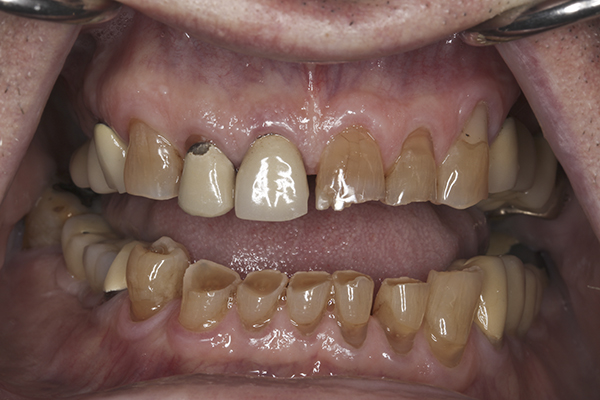

(6.) Preoperative right lateral, open view.

Figure 6

(7.) Preoperative anterior, open view. Note the significant amount of wear, erosion, and abfraction lesions.

Figure 7

(8.) Preoperative left lateral, open view.

Figure 8